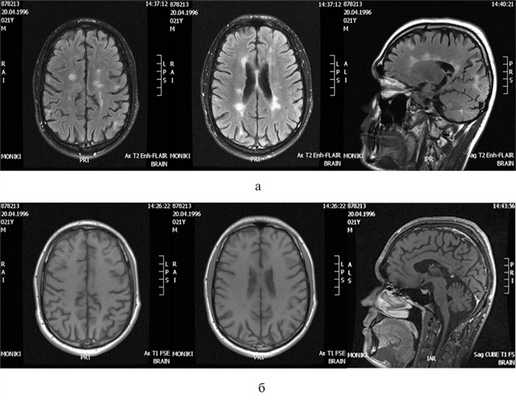

В ноябре 2017 г. появилась продуктивная симптоматика в виде галлюцинаций: слышал императивного характера «голоса в голове», говорил, что «его ногами кто-то управляет, они несут его под машину», стал неуправляемым, настороженным, злобным, временами тревожен, занят своими переживаниями. На МРТ головного мозга (29.11.17): очаги демиелинизации без признаков активности процесса, отмечалась положительная динамика по сравнению с предыдущим исследованием в виде отсутствия активных очагов и уменьшения размеров очагов в правой гемисфере мозжечка.

Титр антител к JCV — 0,53. Пациент ушел из дома 8.12.17 и пропал. Через 3 сут был обнаружен поисковым отрядом в Москве возле школы, где ранее учился, при встрече с матерью ее не узнал. С диагнозом «острое полиморфное психотическое расстройство» был госпитализирован в психиатрическую больницу, где ему было начато лечение нейролептиками, транквилизаторами, антидепрессантами, продолжена терапия противоэпилептическими препаратами. С целью исключения прогрессирующей фокальной лейкоэнцефалопатии (ПМЛ) 13.03.18 проведено повторное МРТ-исследование, где было установлено отсутствие очагов с признаками нарушения целостности ГЭБ, отсутствие признаков ПМЛ, выявлена положительная динамика в виде уменьшения размеров и количества очагов (рис. 3). Рис. 3. МРТ головного мозга больного П. (вне обострения). а — Т2-ВИ-FLAIR; б — Т1-ВИ, контрастирование гадолинием.

В связи с отсутствием признаков обострения по данным нейровизуализации и изменений, характерных для ПМЛ, пульс-терапия ГКС не проводилась, продолжена терапия НЗ. В настоящее время проведено 14 инфузий препарата. Пациент продолжает принимать нейролептики, транквилизаторы, препараты вальпроевой кислоты, на фоне которых продуктивная симптоматика частично регрессировала. Больной ориентирован в пространстве и личности, бредовые идеи активно не высказывает, отрицает наличие «голосов», мышление малопродуктивное, непоследовательное, память на текущие события снижена. В неврологическом статусе отмечается легкая гемигипестезия справа, умеренный атаксический синдром, тазовые расстройства, показатель по EDSS — 5,0 балла, тяжесть состояния преимущественно обусловлена снижением когнитивных функций.

Первый эпизод острых психотических нарушений у пациента П., вероятно, был спровоцирован обострением РС и наличием множественных обширных очагов с признаками нарушения целостности ГЭБ. Второй эпизод отмечался при отсутствии признаков активности процесса и частично регрессировал без применения ГКС. Наличие ПМЛ, которая может дебютировать в виде когнитивных проявлений, было исключено с помощью МРТ и невысокого титра антител к JCV в сыворотке крови. Исходя из вышеизложенного, в данном случае наиболее вероятно сочетание РС и эндогенной психической патологии.